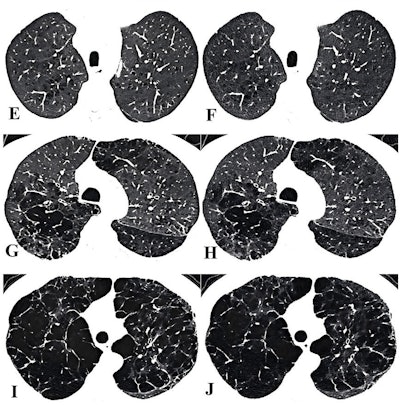

Visual assessment of centrilobular emphysema (CLE) severity on representative axial chest CT images (window width, 700 HU; window level, -750 HU) obtained with low-dose (LD) (left) and ultra-low-dose (ULD) (right) protocols at inspiration in participants with chronic obstructive pulmonary disease. (A) LD and (B) ULD images in a 69-year-old woman. Readers categorized the participant as having trace CLE (lucencies occupying < 0.5% of the most severely affected lung zone) for both scans. (C) LD and (D) ULD images in a 74-year-old man. Readers categorized the participant as having mild CLE (lucencies occupying 0.5% to 5% of the most severely affected lung zone) for both scans.Images and caption courtesy of the RSNA.

(E) LD and (F) ULD images in an 83-year-old man. Readers categorized the participant as having moderate CLE (lucencies occupying >5% of the most severely affected lung zone) for both scans. (G) LD and (H) ULD images in an 83-year-old man. Readers categorized the participant as having confluent CLE for both scans. (I) LD and (J) ULD images in a 61-year-old man. Readers categorized the participant as having advanced destructive CLE for both scans.Images and caption courtesy of the RSNA.